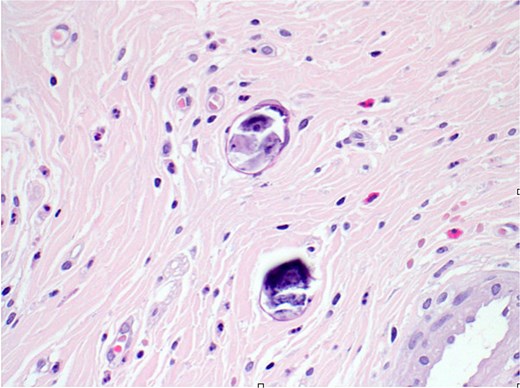

Final histopathological examination revealed the appendix shows focal transmural deposition of calcified Bilharizial ova on the background of acute suppurative appendicitis with periappendicitis (Fig. 4a and b).

(a) H&E stain (2×) revealed the appendix shows extensive transmural deposition of calcified Bilharizial ova on the background of acute suppurative appendicitis with periappendicitis. (b) H&E stain (20×) revealed the appendix shows extensive transmural deposition of calcified Bilharizial ova on the background of acute suppurative appendicitis with periappendicitis.